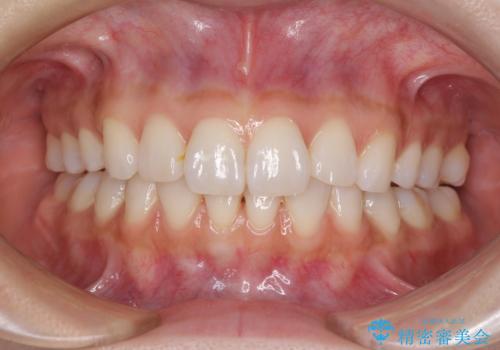

ワイヤーによる全体的ながたつきの矯正治療